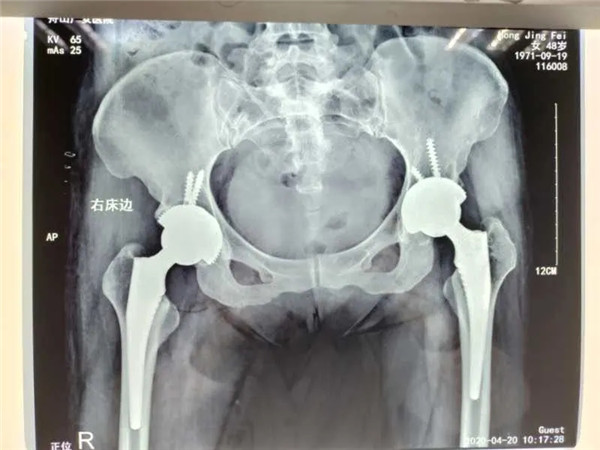

4月13日,危立軍副院長為洪女士實施了右側(cè)髖關(guān)節(jié)置換術(shù),手術(shù)在關(guān)節(jié)鏡下完成,術(shù)后洪女士感覺良好。術(shù)后一周,洪女士便可以下地行走。目前,洪女士恢復(fù)良好,已經(jīng)出院回家休養(yǎng)。

雙側(cè)髖關(guān)節(jié)置換

值得一提的是,對于此次手術(shù)的人工關(guān)節(jié)材料,洪女士仍舊和三年前一樣,選擇了全陶瓷人工關(guān)節(jié)。

據(jù)危立軍副院長介紹,金屬、陶瓷和聚乙烯是目前人工關(guān)節(jié)假體的主要制作材料。而相對于另外兩種,全陶瓷人工關(guān)節(jié)假體的硬度最大、最耐磨。陶瓷的特點是硬度大,超耐磨,有一定的脆性。很多股骨頭壞死的病人都存在一個誤區(qū),就是擔(dān)心人工關(guān)節(jié)使用壽命不高(以前的高分子容易磨損,平均使用壽命15年),對于病癥能拖盡可能拖,往往等到疼痛難忍了才選擇開刀做手術(shù),錯失了最合適的手術(shù)時間,大大降低了生活質(zhì)量。隨著第四代陶瓷關(guān)節(jié)的出世,使用壽命可達50年,是股骨頭壞死患者的福音。